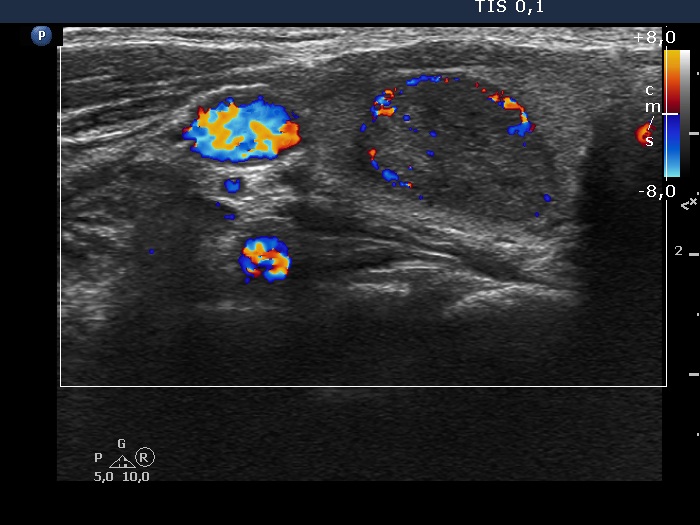

Right lobe, longitudinal scan

Right lobe, transverse scan, color Doppler mode. The lesion has perinodular blood flow.